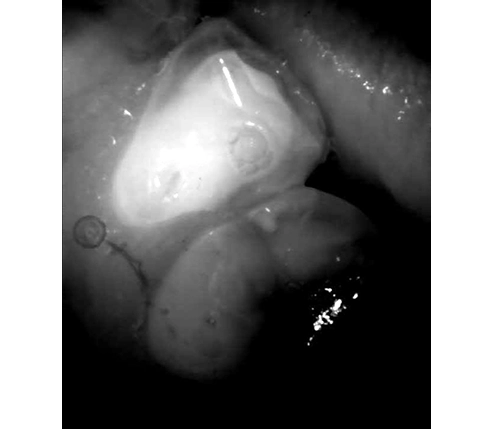

Caries lesion on a mesial surface of UR5, barely visible on (1) Intraoral camera image and a (2) bitewing X-ray, can be clearly identified on the (3) iTero™ NIRI technology (Near Infra-Red Imaging) images. (4) Caries lesion confirmed clinically. Images are courtesy of Dr. Einfeldt.

Reviewing scans with an intraoral camera and iTero™ NIRI technology (Near Infra-Red Imaging) images that iTero™ takes automatically is what I always do. Sometimes, the X-rays are not ideal if the angle is not right or an overlap occurs, so the NIRI in my hands is more sensitive. NIRI has helped me find caries that X-rays didn’t show. Despite years of experience, magnification, and good light, interproximal caries are hard to detect. NIRI images from iTero highlight it and help me decide when to treat it.